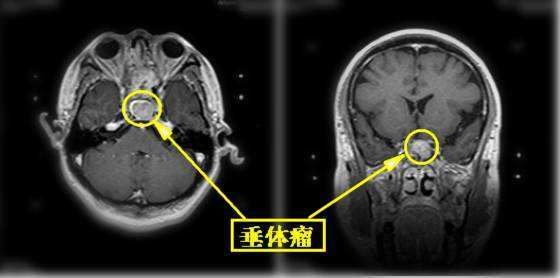

经过详细检查,深圳市人民医院神经外科 蔡坤皓主任跟钟女士说:“你这不是什么神经性头痛,是垂体瘤,就是你脑子里长了一个东西,压迫了神经,才让你这么痛的。这个瘤太大了,吃药控制不了,只能手术。”

一开始钟女士听到【垂体瘤】三个字,一脸迷惑,这是什么病?其实,垂体瘤是一个长在垂体上、而且是神经系统常见的肿瘤,占颅内肿瘤10%~20%,多数为良性,微创手术是首选治疗方法。